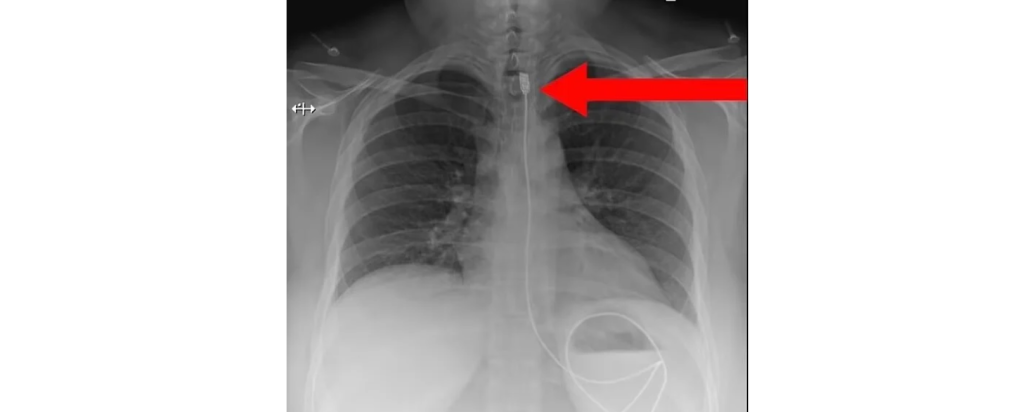

-

Kένι Νταλγκλίς: Ο «θρύλος» της Λίβερπουλ διαγνώστηκε με καρκίνο – Τι ζήτησε από τον κόσμο και τα ΜΜΕ